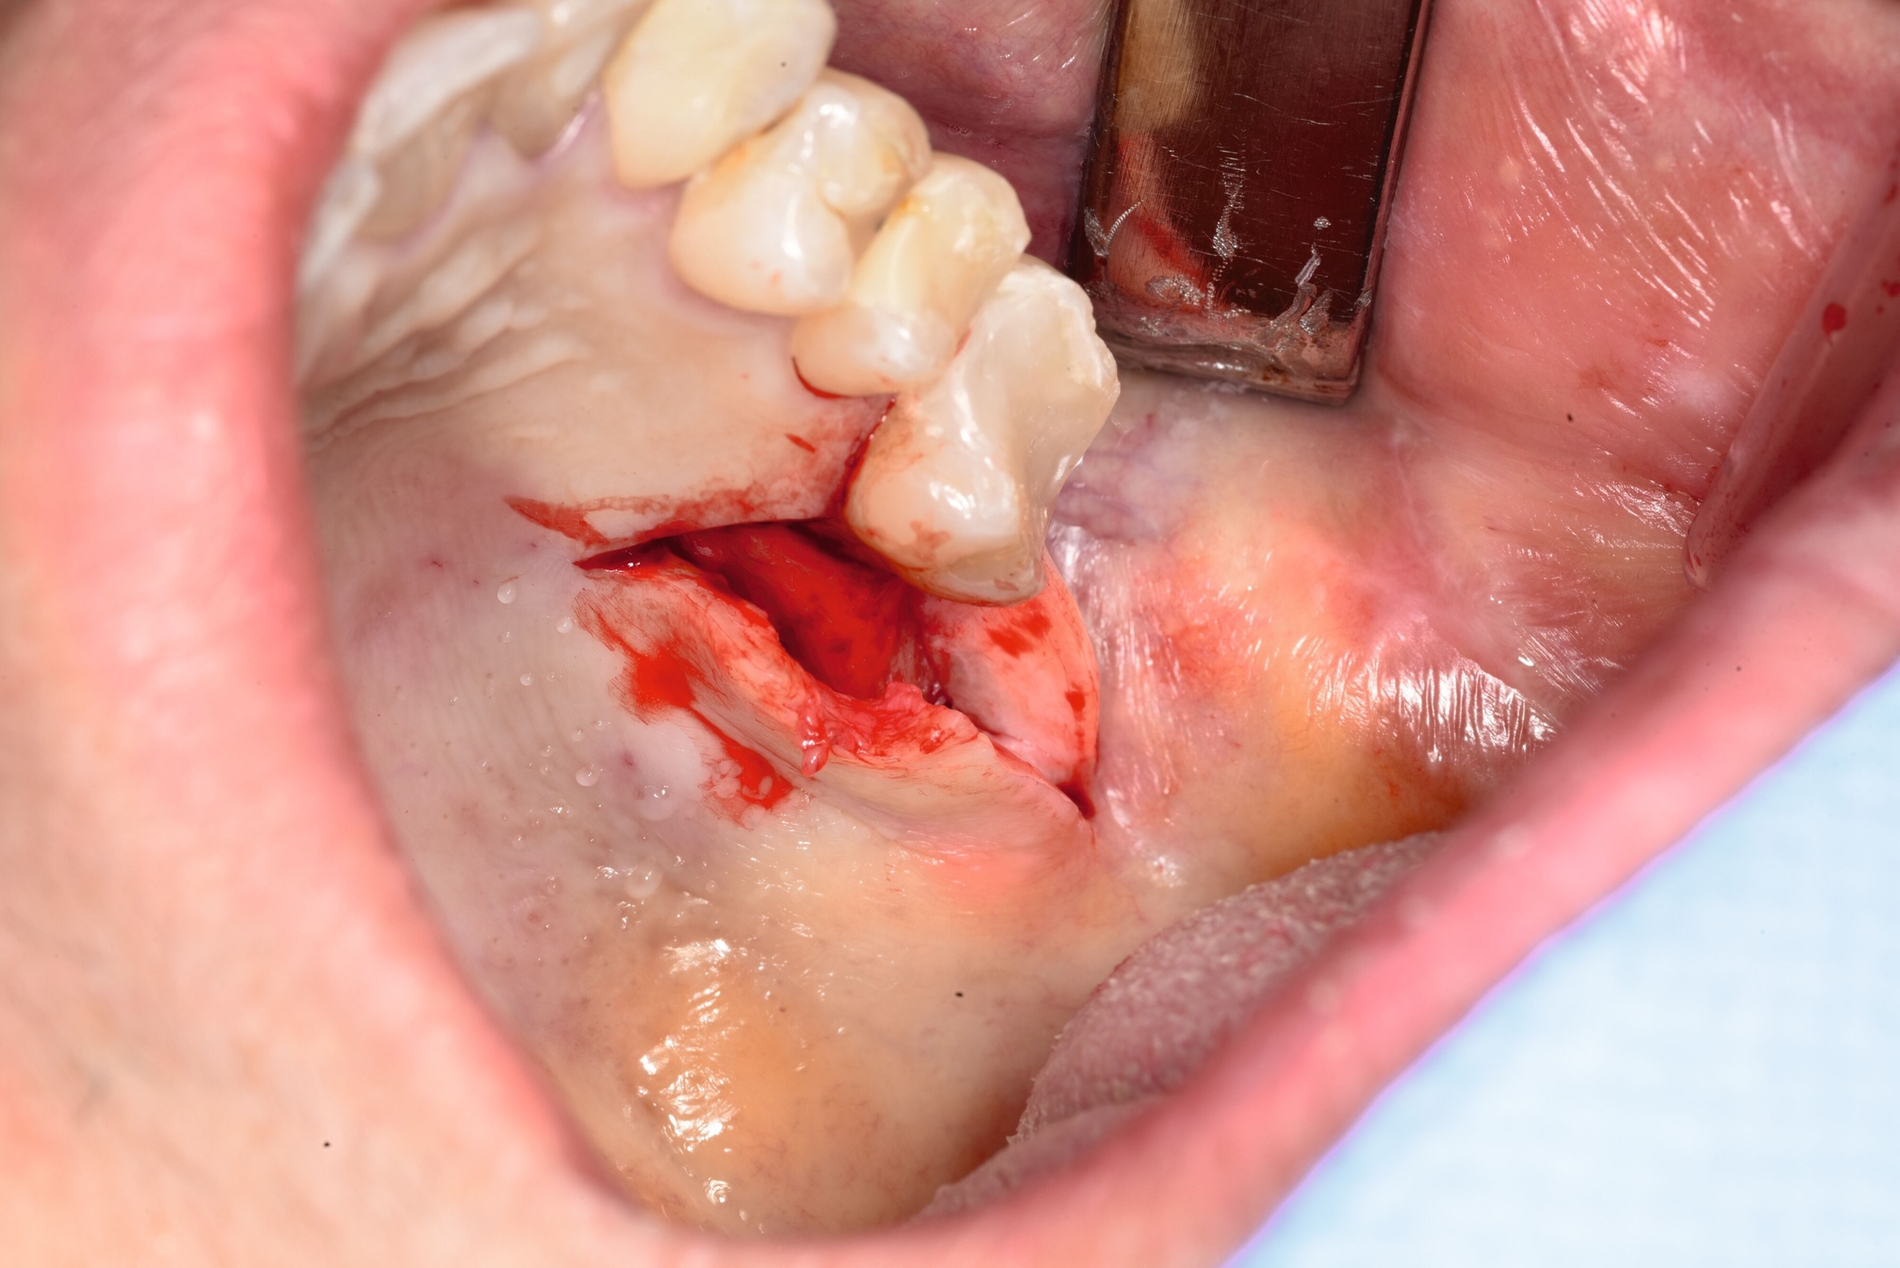

Der Zugangsweg wurde palatinal gewählt. Nach systemgerechter Kalibrierung erfolgte zunächst eine navigationsgestützte Orientierung, da sich der klinische Situs intraoral komplett reizlos und ohne sichtbare Lagehinweise präsentierte (Abbildung 3). Eine Markierung mit dem Rosenbohrer auf der Schleimhaut diente der exakten Referenz für die Lappenschnittführung (Abbildung 4). Präoperativ wurde zudem eine Verbandsplatte für den Gaumen angefertigt, um die postoperative Stabilisierung zu erleichtern.

Die Schnittführung erfolgte krestal mit einer palatinalen Entlastung (Abbildung 5). Anschließend wurde der knöcherne Zugang zur Kieferhöhle unter kontinuierlicher Navigation gezielt osteotomiert (Abbildung 6). Das Navigationssystem ermöglichte dabei eine präzise Lokalisation des Fremdkörpers und erhöhte die Sicherheit in Bezug auf die angrenzenden Strukturen. Nach vorsichtiger, schrittweiser Osteotomie unter Navigationskontrolle (Abbildung 7) konnte das frakturierte Wurzelkanalinstrument schließlich sicher dargestellt und entfernt werden (Abbildung 8). Zur Auffüllung des entstandenen Defekts wurde ein mit PRF (Mectron®-Verfahren) getränktes Knochenersatzmaterial (Bio-Oss Collagen®, Geistlich®) eingebracht (Abbildung 9). Der Wundverschluss erfolgte spannungsfrei mittels Seidennaht 3-0 (Abbildung 10).